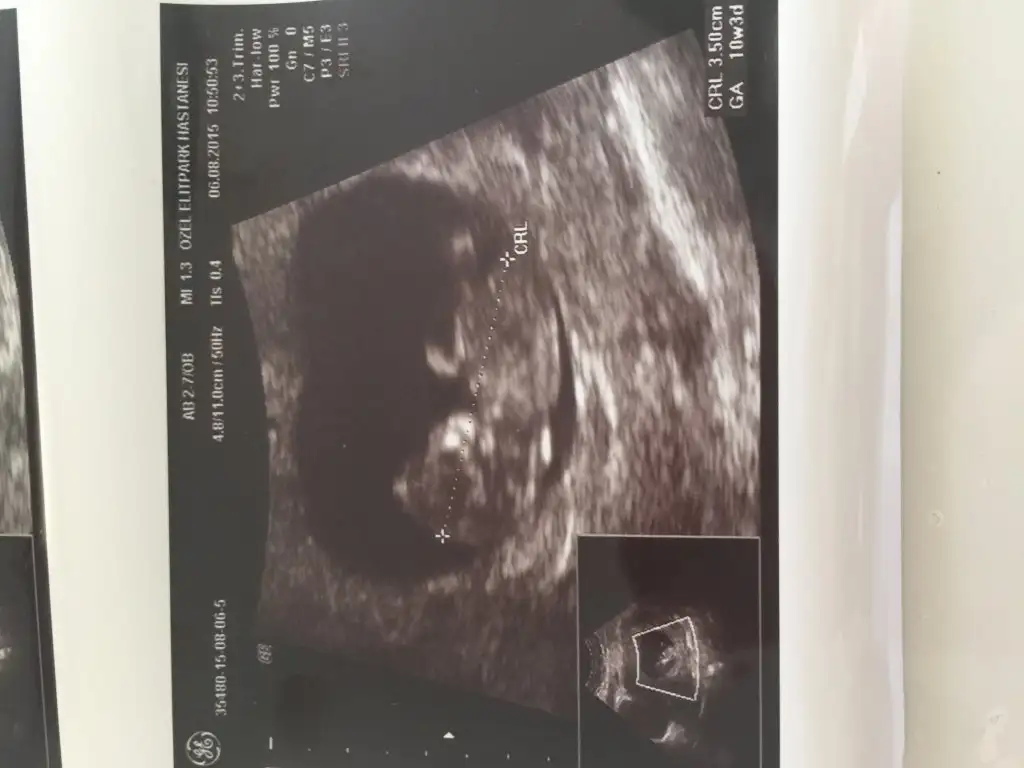

İnş bebeğini sağlıcakla kucağına alırsın benim merak etiğim bir konu var sen bilebilirsin cevabını kalp durması anlaşılıyor mu belirti veriyor mu kanama gibi mesela kaçıncı hafta da oldu bende belirtilerim kesildi gibi olduğunda en çok ondan korkuyorum aklıma takıyorum belirti verir mi.merak ediyorumBenim daha önce iki gebeliğim kalp durması yüzünden sonlandı o yüzden kullanıyorum gebelik iyi gidiyor biraz bulantım var ama göbeğim çok çıkmış kendimi beş aylık hamile gibi görüyorum şişkinlik var yani gaz sıkıntım var şimdiden dokuzuncu aya kadar ne yapacam bilemiyorum

Maalesef kalp durmasi durumunda (missed miscarriage) hic bir ipucu olmuyor, vucut atmayi da bilemiyor. Bana oldugunda zaten cok az belirtim vardi, kendimce killandim ama anlayabilecegim bir sey olmamisti. (Buna ragmen sonunda dusuk olup ustune de ameliyat olunca bile hormonlarim o kadar yuksekmis ki, hormonlarimin dusup tekrar adet olmam 4-5 ayi buldu (yani belirtim olmamasiyla iliskili degilmis). Bazi kisilerde de plasenta olusuyor, hormonlar normal olarak calismaya devam ediyor, belirtiler hic bir zaman durmuyor, sadece ultrasonda sorun oldugu belli oluyormus. Yani belirtilere bakarak iyi gidip gitmedigini anlayamiyoruz. Belirtiler birden bicak gibi kesilirse ve geri gelmezse bi doktora gorunmekte fayda var ama bu kotu gidiyor demek degil, ayni sekilde belirti olmasi da iyi gittiginin garantisi degil. (Simdi boyle diyerek belirtilerin varken de korkmana sebep olmak istemiyorum, aman ha). Duzenli tetkikler disinda baska hic bir bilgi kaynagimiz yok. Ben de hem bir ise yaramadigini biliyorum, hem de butun gun 'su anda midem bulaniyor mu' 'bakayim goguslerim agriyor mu' diye dusunup duruyorum.İnş bebeğini sağlıcakla kucağına alırsın benim merak etiğim bir konu var sen bilebilirsin cevabını kalp durması anlaşılıyor mu belirti veriyor mu kanama gibi mesela kaçıncı hafta da oldu bende belirtilerim kesildi gibi olduğunda en çok ondan korkuyorum aklıma takıyorum belirti verir mi.merak ediyorum

Geçmiş olsun canım inş bebişini sağlıcakla kucağına alırsın Allah'ım bize hayırlı evlatlar versin!!!Benim daha önce iki gebeliğim kalp durması yüzünden sonlandı o yüzden kullanıyorum gebelik iyi gidiyor biraz bulantım var ama göbeğim çok çıkmış kendimi beş aylık hamile gibi görüyorum şişkinlik var yani gaz sıkıntım var şimdiden dokuzuncu aya kadar ne yapacam bilemiyorum